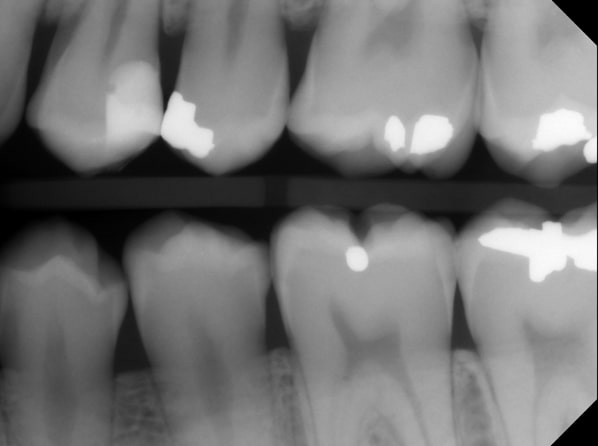

Typically, a post-op bitewing is taken to confirm the proper adaptation of restorative material to tooth structure, mainly when deep margin elevation is used to elevate a margin for indirect restorations. Deep margin elevation can be utilized near the bone with negligible effects on the biologic width when performed in a limited area.

In some cases, the matrix band may need to be adapted to accommodate the prep’s subgingival aspect. A #2 Tofflemire band or a modified #1 Tofflemire band can extend the matrix to ensure an adequate seal of the margin elevation material to the tooth.

Deep margin elevation has been shown to provide predictable long-term survival rates up to a decade after its performance. It’s yet another tool in our toolbox for managing subgingival preparations.